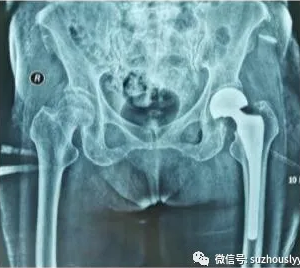

术后第1天安排床旁摄骨盆正位X线片,显示假体大小匹配完美、假体股骨柄完全中置。

手术骨盆正位片